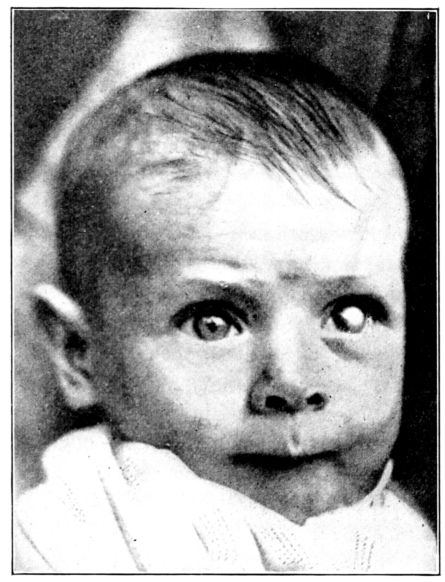

| 140. | Baby partially blind as a result of a faulty diet | 378 |